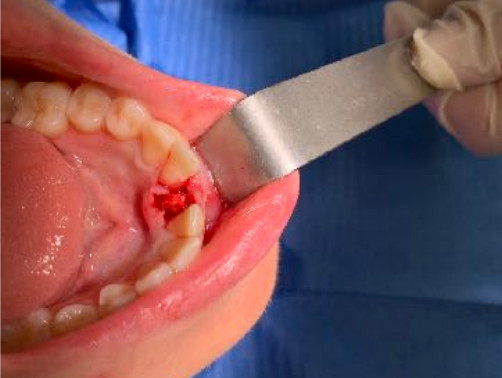

Il diametro ridotto del collo consente di mettersi al riparo da eventuali periimplantiti e migliora nettamente la velocità della guarigione. In questo caso è stato maschiato con un diametro 4 ed è stato inserito un impianto di Tramonte diametro 4 mm a 7 spire a collo corto . Il titanio utilizzato è sempre di grado 4.

| Situazione estrattiva: Impianto postestrattivo immediato a carico immediato. | Densità secondo Misch: D2 |

| Sequenza frese: Solo fresa lanceolata | Sequenza maschiatori: maschiatore diametro 4 mm |

| Carico occlusale: immediato leggero. | |